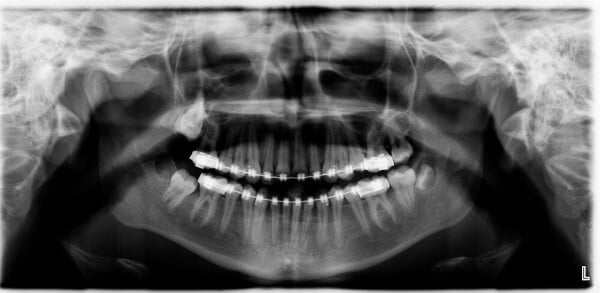

Bei der Weisheitszahnentfernung ist eine gründliche Voruntersuchung von entscheidender Bedeutung. Durch eine umfassende Voruntersuchung und die Verwendung eines dreidimensionalen DVT-Röntgenbildes kann der Zahnarzt oder Oralchirurg die genaue Lage der Weisheitszähne präzise bestimmen und den Eingriff planen. Dies minimiert das Risiko einer Verletzung des sensiblen Unterkiefernervs und verringert die Gefahr einer vorübergehenden Taubheit der Unterlippe. Während des Eingriffs erfolgt in den meisten Fällen ein Schleimhautschnitt, gefolgt von der Freilegung der Zahnkrone, der möglichen Teilung des Zahns und der Entnahme der einzelnen Zahnteile. Abschließend wird die Wunde mit Nähten verschlossen.

Fälle, in denen Menschen von nachwachsenden Weisheitszähnen berichten, sind in der Regel auf bei den Röntgenaufnahmen „übersehene“ Weisheitszähne, Hyperdontie (d.h. es sind mehr als vier Weisheitszähne im Kiefer angelegt) oder im Kiefer verbliebene Wurzelstücke, die mit den Jahren an die Oberfläche wandern, zurückzuführen.

Wenn Sie also das Gefühl haben, dass ein entfernter Weisheitszahn „nachwächst“, sollten Sie die Situation umgehend mit Ihrem Zahnarzt oder Kieferchirurgen besprechen und eine erneute Röntgendiagnostik in Betracht ziehen.